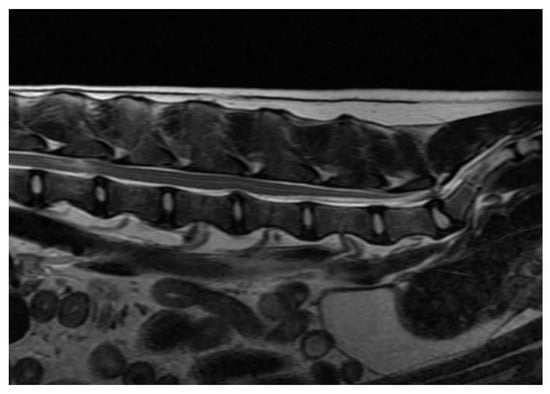

3.2. Diagnostic Imaging